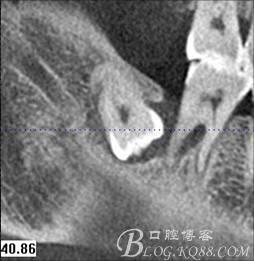

圖3.通過矢狀面和冠狀面來判斷48與下頜管及47的關系

圖1. 47牙冠的近中面緊鄰下頜神經管

48未萌出,47遠中可探及深約7mm的牙周袋。頰側47、48之間牙齦紅腫,有少量血性滲出。X線根尖片顯示:48牙冠反轉倒置,47遠中牙槽骨吸收明顯。CBCT顯示:48牙冠近中面位于下頜管內。